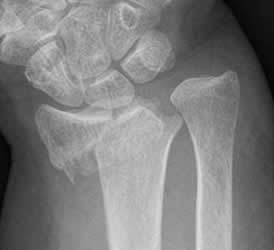

Fig 43. Angulación en valgo.

Rx AP. Fractura del radio distal, con desplazamiento lateral del fragmento distal.